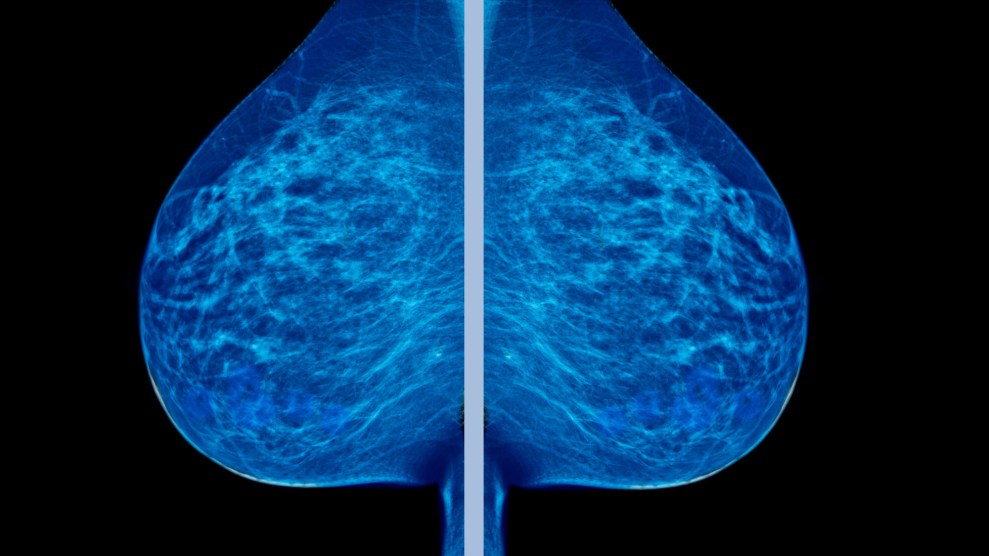

I thought I’d done everything right: breastfeeding my children, a careful diet, plenty of exercise. I wasn’t overweight and didn’t have a family history. I bought BPA-free bottles for my filtered water. But on a visit to the radiology department last spring, a pair of red brackets highlighted something worrisome on the ultrasound monitor.

Invasive lobular carcinoma—a malignant breast tumor. This spidery little beast measuring nearly three centimeters meant I had stage 2 cancer.

At 47, I was a decade and a half younger than the median age for breast cancer diagnosis in the United States. Was this just bad luck? Maybe, but the journalist in me was still curious to know: Why me? So I dug into the literature on risk factors to see where I might have fit in. It’s an impossible question to answer definitively for an individual, like trying to prove that a single weather event was caused by climate change. As one doctor told me, “You know who’s at risk for getting breast cancer? People with breasts!”

A few months ago, I plugged my data into the National Cancer Institute’s breast cancer risk calculator to see what my odds had been before I discovered my tumor. The bare-bones assessment showed I had a 1.1 percent risk of getting breast cancer in the next five years. The calculator doesn’t account for my alcohol consumption (or the protective effects of exercise and breastfeeding), but the experts I’ve spoken with say booze probably bumped up my risk.